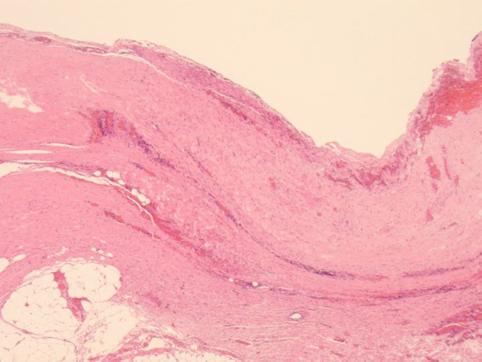

疾病(病理主体)的分类良性非上皮性肿瘤/囊肿

部位(按器官分)食道/下

检查方法病理切片(微观)

肿瘤最大直径40以上